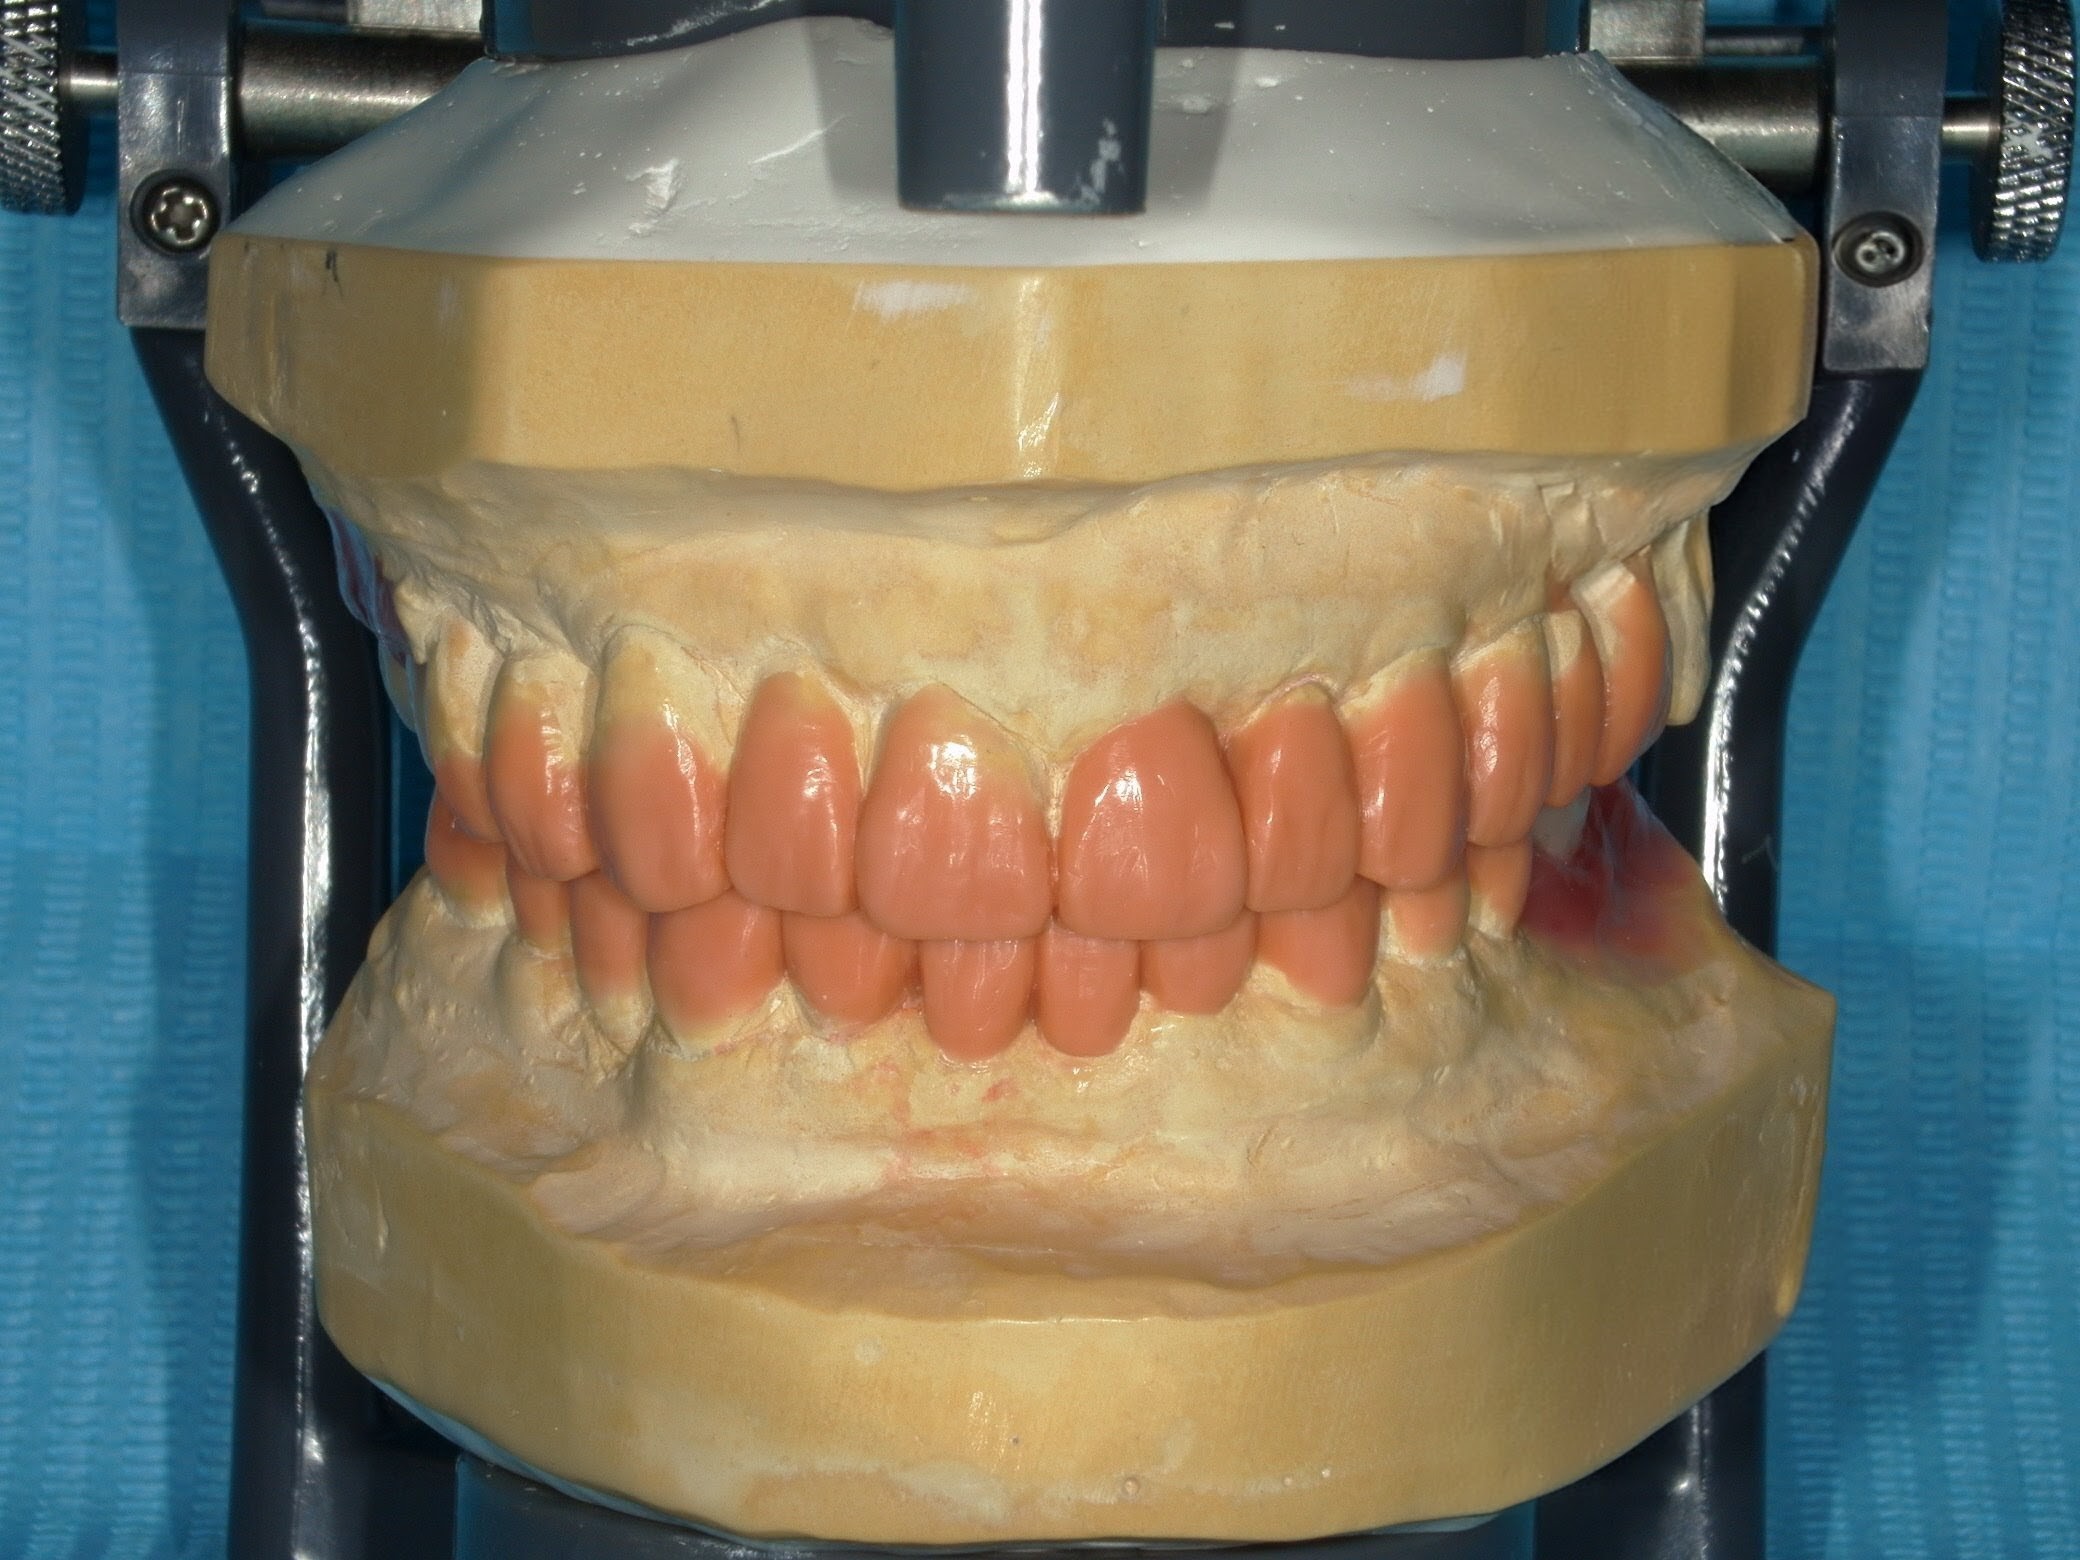

治療前に最終形態を設計し、

噛み合わせや力のバランスまで確認したうえで治療を進めます

※治療前に作成するワックスアップ(最終形態の設計)

ワックスアップにより最終形態を設計し、

噛み合わせや力のコントロールを含めて治療しています。